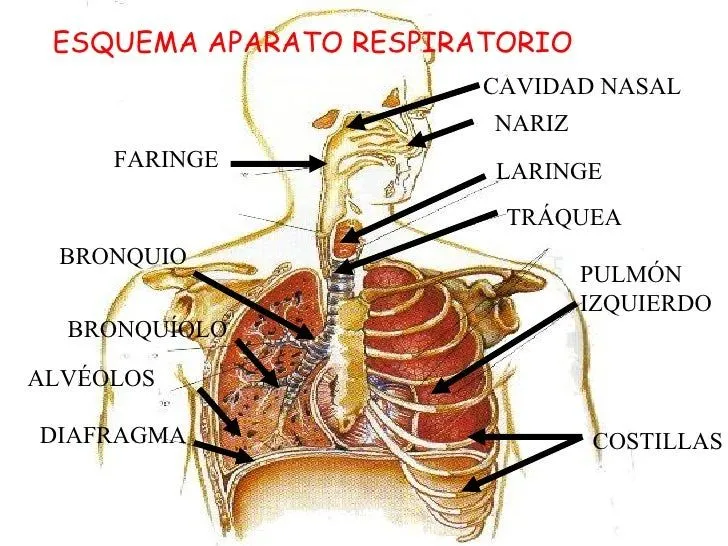

Esquema del aparato respiratorio, Órganos del aparato respiratorio ...

Indica el motivo para eliminar esta imagen: